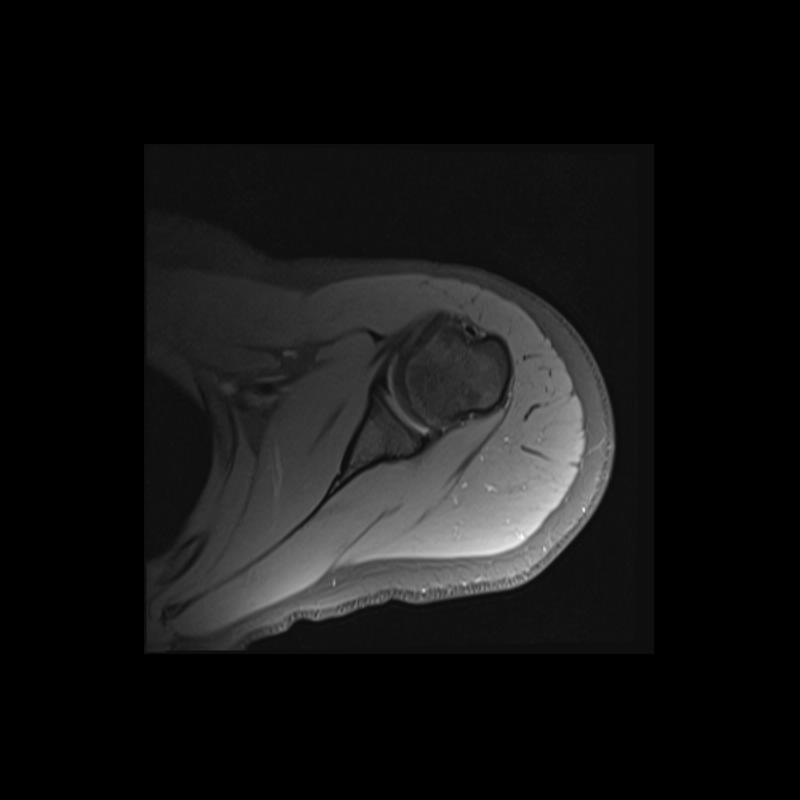

Shoulder MRI Anatomy